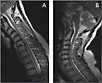

NeuroSwing is a new positioning and movement system for dynamic magnetic

resonance imaging (MRI) examinations of the cervical spine. The system was

developed by Hightech Electronic GmbH in cooperation with Siemens Medical

Solutions. The continuously variable, smooth movements of the NeuroSwing for

the first time enable dynamic MR acquisitions of the cervical spine to be

performed in anteflexion, retroflexion, lateral flexion, and rotation,

either separately or in combination.